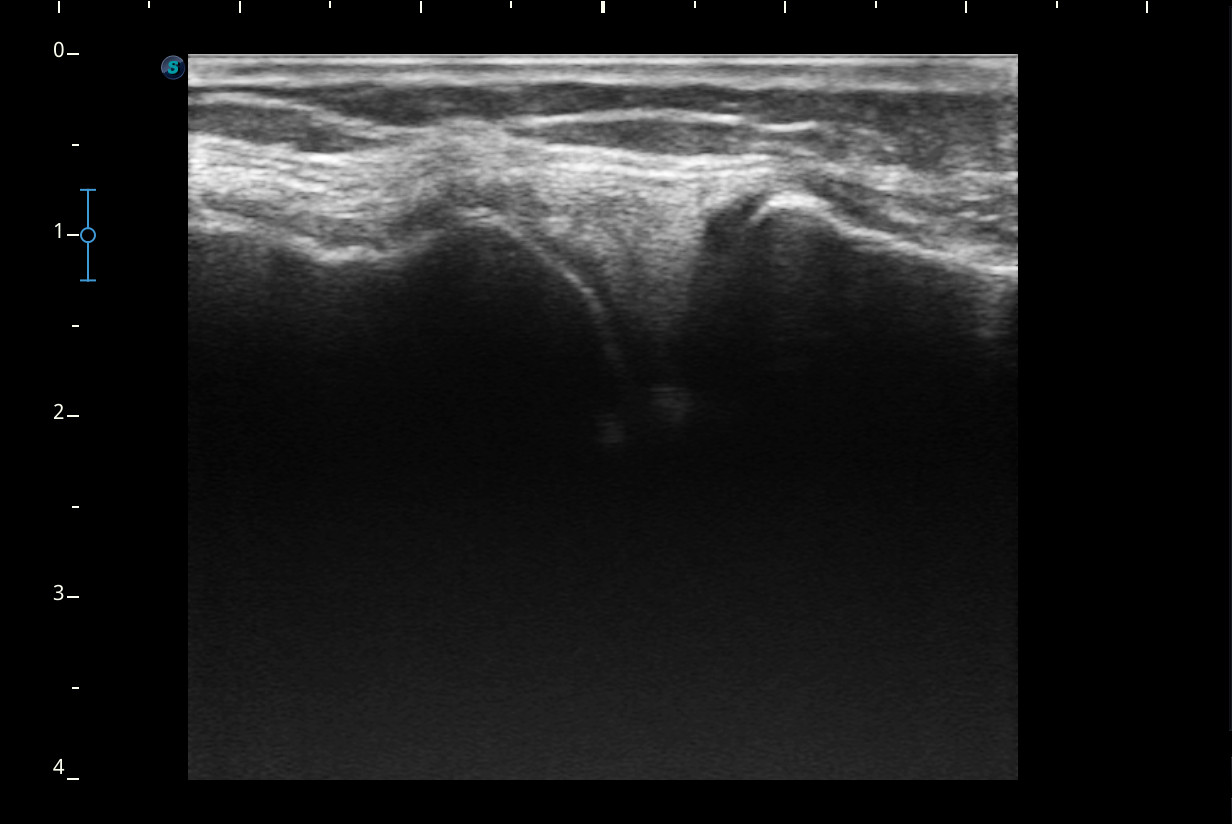

Se realiza ecografía de rodilla.

Descripción de los hallazgos ecográficos y las imágenes más relevantes para la resolución del caso

Rodilla sin derrame articular. No se aprecian lesiones en Ligamentos colaterales. Ligamento rotuliano sin hallazgos valorables. Rotura menisco interno y dudosa fisura menisco externo. Tendones rotuliano y cuadricipital normales.